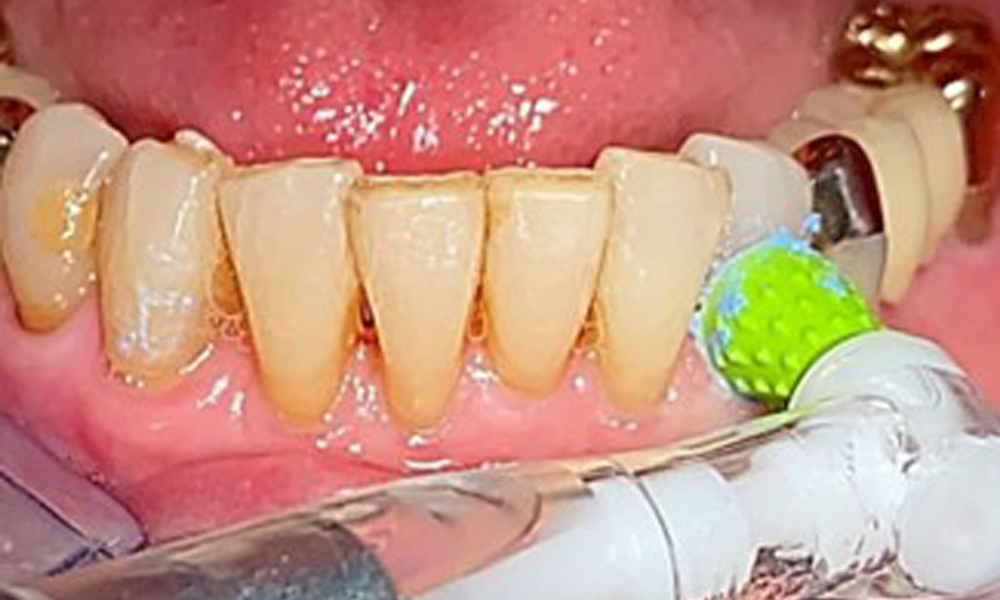

Für die Restaurationsränder und Zahnzwischenräume und Implantatoberflächen kann das Pulverstrahlgerät mit einem niedrig-abrasiven Pulver zum Einsatz zur Entfernung von Biofilm kommen (Abb. 12). Durch selektives Polieren (Abb. 13) sollte eine Glättung aller weniger sensiblen Bereiche erfolgen, da die bakterielle Wiederanhaftung reduziert wird. (9)

Eine Zahnzwischenraumreinigung mit Interdentalbürstchen (Abb. 9) oder Zahnseide ist ebenso erforderlich genauso wie die Zungenreinigung. Wichtig ist auch in der Praxis die Prothese professionell im Ultraschallbad und ggf. mit desinfizierenden Lösungen zu säubern, um Pilzinfektionen entgegenzuwirken. Verfärbungen sind dadurch ebenso entfernbar und geben ein sauberes Gefühl für die Patientin.